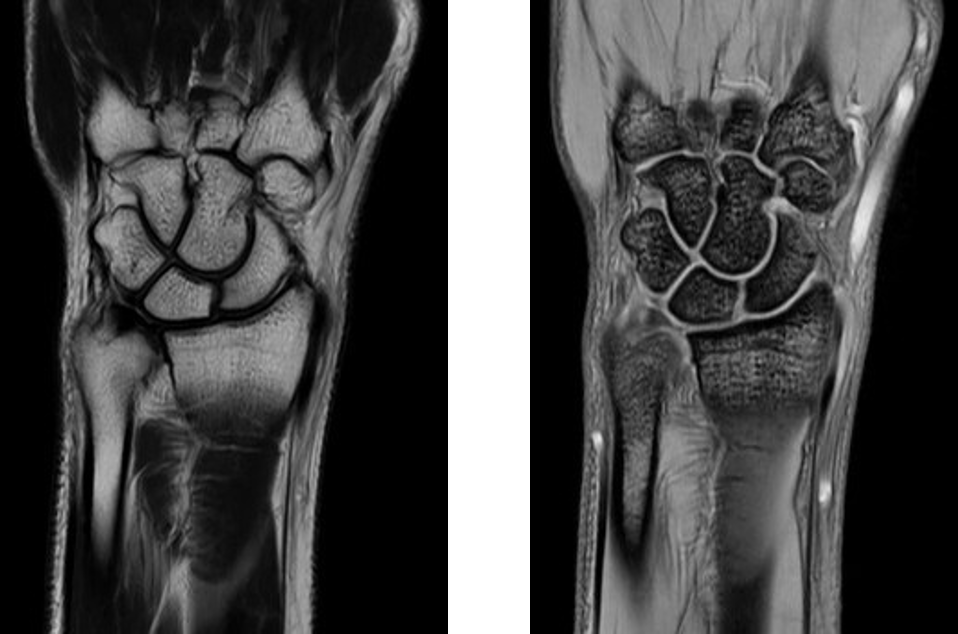

整形領域の撮影

当センターでは、体幹部のみならず四肢の撮影も行っております。膝関節、肩関節、手関節、足関節など整形領域の撮影も行っております。最新のAI技術を用いることで、より細かく描出できるようになり、靭帯損傷や骨折、筋損傷を見つけることが出来ます。

『手関節MRI画像』